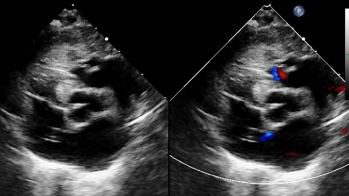

Vidéo 1

Vidéo 2

Vidéo 3

Vidéo 4